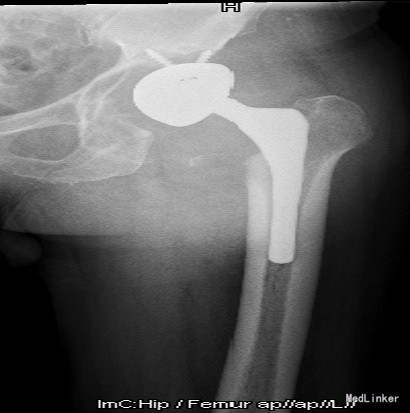

查体:左腹股沟区可见瘢痕及色素沉着,左腹股沟区可触及质硬包块,触之胀痛,局部皮温正常,左下肢内侧皮肤麻木。左髋外展10°,内收10°,屈曲80°,伸0°,内旋0°,外旋5°,右髋外展20°,内收15°,屈90°,伸0°,内旋10°,外旋10°,双髋内、外旋活动诱发疼痛;双下肢基本等长,双侧4字试验(+)。 辅助检查:双髋内、外旋活动诱发疼痛;双下肢基本等长,双侧4字试验(+)。X线片:左髋THA后假体向上移位,右侧股骨形态失常,关节间隙变窄

诊断:1.左侧THA术后假体松动、聚乙烯内衬磨损、炎性假瘤形成 2.左侧THA术后髋臼及股骨近端骨溶解 3.左侧THA术后髋臼及股骨近端骨缺损(髋臼AAOS III型 股骨Paprosky II型) 4.右髋重度骨关节炎 5.高血压 (2期 高危) 治疗:完善检查,调整患者全身条件后在全麻下行左侧全髋关节假体取出+炎性假瘤切除+异体骨植骨+髋臼重建+人工全髋关节翻修术,术中发现:左髋关节囊后外侧炎性假瘤形成,与关节腔相通,内有大量咖啡色混浊液体,髋臼及股骨近端骨溶解导致骨缺损,以髋臼前壁及下壁和股骨近端严重,小转子消失,关节腔周围大量炎性坏死组织。髋臼假体松动。术中安放左侧Zimmer64mmCage,并用8枚不同长度螺钉固定可靠,Cage内放骨水泥后安放外径59mm,内径28mm聚乙烯内衬并调整前倾及外展角度合适,股骨侧安放12#加长股骨柄,28mm直径、+1.5颈长陶瓷股骨头。